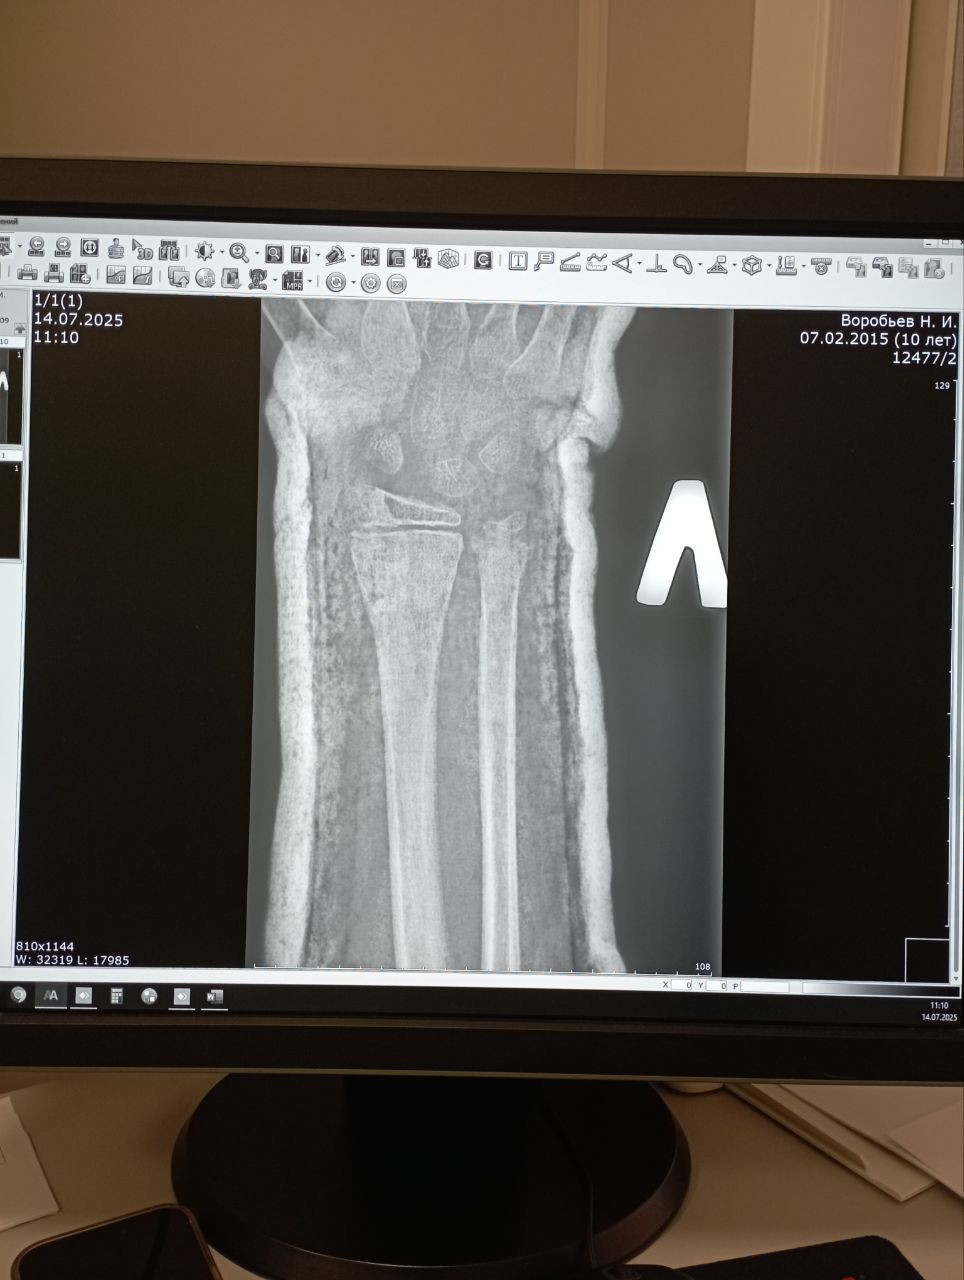

Здравствуйте. По рентгеновским снимкам видно, что перелом в области дистального метафиза лучевой кости с выраженным смещением начал формировать костную мозоль, однако линия перелома еще частично просматривается. Процесс сращения идёт, но до полноценной консолидации требуется время. Снимать гипс на 28-й день пока рано без очной оценки хирурга или травматолога. Обычно такие переломы фиксируют на 4-6 недель, в зависимости от возраста, общего состояния и стабильности отломков. Рекомендую: